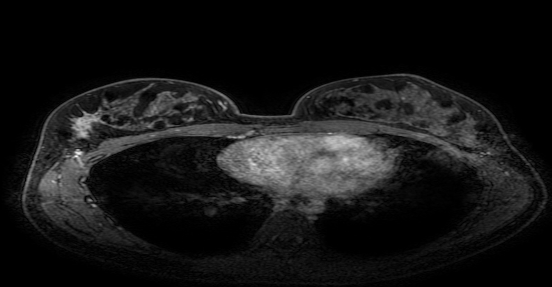

• 乳腺+腋窝淋巴结超声(2023年10月6日 ):双乳腺增生症;右乳多发实性结节(BI-RADS-4a);左乳多发实性结节(BI-RADS-3);右侧腋中、下组多个淋巴结肿大(建议活检);左侧腋窝多个淋巴结可见,个别淋巴结肿大。

图 2023年10月6日乳腺+腋窝淋巴结超声